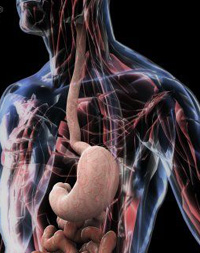

Ахалазия кардии – это хроническое заболевание нервно-мышечного аппарата пищевода, которое характеризуется нарушением рефлекторного открытия нижнего сфинктера пищевода у входа в желудок во время глотания. Это сопровождается нарушением перистальтики пищевода. В результате затрудняется прохождение пищи в желудок.

Больной жалуется на срыгивание только что съеденной пищей. Появляются боли, носящие самый разнообразный характер: от разлитой боли в грудной клетке до локализованной в одной точке. Боли могут отдавать в плечо, шею, лопатку, ухо и т.д. Болевые ощущения появляются после еды, но часто боли могут не зависеть от приема пищи. С течением времени болевой синдром уменьшается. Больные точно указывают место задержки пищи на передней поверхности грудной клетки. Часто пациенты, чтобы облегчить прохождение пищевого комка, выпивают большое количество жидкости, наклоняют туловище, держатся руками за шею или за грудину. Отрыгивания ( регургитация) вначале появляется сразу после приема пищи, затем, вследствие расширения нижнего отдела пищевода, там накапливается большой объем пищи, которая отрыгивается уже позднее (сразу большой объем). Такое состояние иногда называют пищеводной рвотой (без примеси кислого содержимого желудка). Отрыгивание пищи может привести к забросу части пищевого комка в трахею и в легкие. Возникают воспалительные заболевания легких (аспирационная пневмония). Иногда у пациента возникают жалобы на упорную икоту. Часто ахалазия кардии сопровождается запорами.

В диагностике важнейшее значение имеют клинические данные и результаты инструментальных исследований. На рентгенографии - отсутствие воздушного пузыря желудка. При контрастировании сульфатом бария определяется расширение пищевода с дистальным клювоподобным сужением и уровнем жидкости.